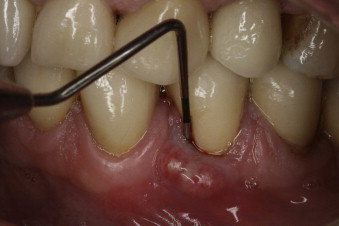

A pocket between the gum and the tooth, near the fracture, where the gum essentially detaches from the tooth